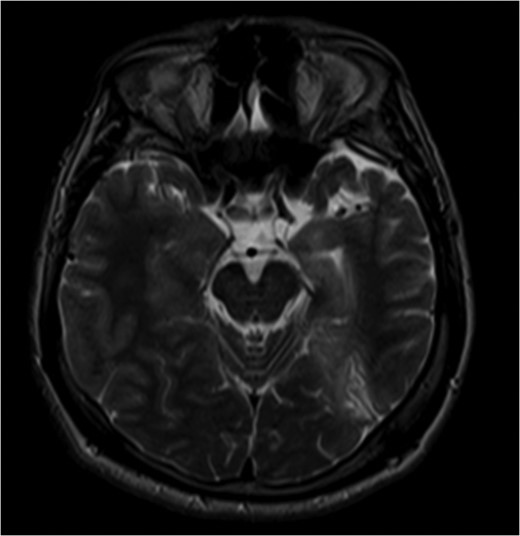

We present a case of a 22-year-old male with history of medically refractory epilepsy since age 7 after suffering from viral encephalitis. He typically has 1–3 seizures per month. Scalp EEG monitoring was able to localize onset to the left temporal lobe and/or left parieto-occipital lobe. Most of the seizures during the study were complex partial with unresponsiveness, orofacial automatisms and right hand twitching. One seizure was atypical, starting with visual changes and appeared to have onset from the left occipital region. MRI was consistent with left mesial temporal sclerosis as well as left parieto-occipital encephalomalacia related to prior encephalitic infarct (Figs 1 and 2). PET scan was pertinent for decreased metabolism in the left mesial temporal lobe. Ictal SPECT was consistent with a left temporal focus. WADA demonstrated left hemispheric language and adequate memory function bilaterally and visual field testing was normal. The patient met criteria for major depressive disorder with psychiatric features on psychiatry evaluation.

Pre-op MRI images. T2 weighted images demonstrate atrophy and hyperintense signal along the left medial temporal lobe.